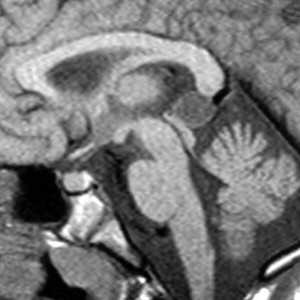

КТ и МРТ головного мозга. Коллоидная киста III желудочка.